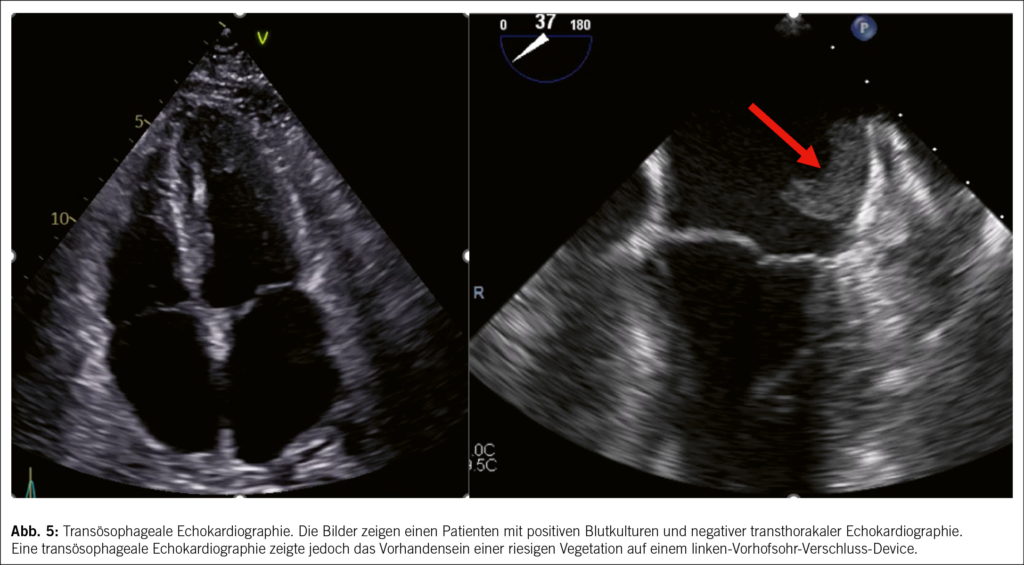

• Was die Echokardiographie anbelangt, so ist die Indikation zur Transoesophageale über die Transthorakale Echokardiographie hinaus inzwischen zu einer Indikation der Klasse I aufgewertet worden. Tatsächlich erlaubt die transoesophageale Echokardiographie bei vielen Patienten eine bessere diagnostische Performance (mit der einzigen möglichen Ausnahme einer isolierten rechtsseitigen Endokarditis) und ermöglicht die frühzeitige Erkennung von Komplikationen, Abb. 5.

• Ein multimodaler Bildgebungsansatz wird dringend empfohlen. Neuere Studien haben gezeigt, dass die kardiale CT-Scan eine sehr gute diagnostische Aussagekraft für die Diagnose von Herzklappenläsionen und perivalvulären Komplikationen bei nativer Klappenendokarditis hat, während die PET-CT eine sehr gute Aussagekraft für die Diagnose von Endokarditis bei Herzklappenprothesen hat (9, 10), Abb. 6 und 7. Die Magnetresonanz Untersuchung ist nicht geeignet, um kardiale Vegetation oder Komplikationen zu erkennen, kann aber nützlich sein, um Fernläsionen zu entdecken.